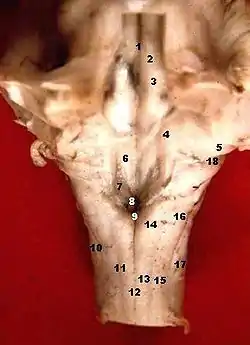

Hind-brain of a human embryo of three months—viewed from behind and partly from left side. (Rhomboid fossa labeled at center.) | |

Rhomboid fossa. | |

The rhomboid fossa is a rhombus-shaped depression that is the anterior part of the fourth ventricle. Its anterior wall, formed by the back of the pons and the medulla oblongata, constitutes the floor of the fourth ventricle.

It is covered by a thin layer of grey matter continuous with that of the spinal cord; superficial to this is a thin lamina of neuroglia which constitutes the ependyma of the ventricle and supports a layer of ciliated epithelium.

The fossa consists of three parts, superior, intermediate, and inferior:

- The superior part is triangular in shape and limited laterally by the superior cerebellar peduncle; its apex, directed upward, is continuous with the cerebral aqueduct; its base is represented by an imaginary line at the level of the upper ends of the superior foveae.

- The intermediate part extends from this level to that of the horizontal portions of the taeniae of the ventricle; it is narrow above where it is limited laterally by the middle peduncle, but widens below and is prolonged into the lateral recesses of the ventricle.

- The inferior part is triangular, and its downwardly directed apex, named the calamus scriptorius (as is shaped like a writing quill-nib)[1] is continuous with the central canal of the closed part of the medulla oblongata.

The sulcus limitans forms the lateral boundary of the medial eminence.

In the superior part of the rhomboid fossa it corresponds with the lateral limit of the fossa and presents a bluish-gray area, the locus coeruleus, which owes its color to an underlying patch of deeply pigmented nerve cells, termed the substantia ferruginea.

At the level of the facial colliculus the sulcus limitans widens into a flattened depression, the superior fovea, and in the inferior part of the fossa appears as a distinct dimple, the inferior fovea.

Lateral to the foveæ is a rounded elevation named the area acustica, which extends into the lateral recess and there forms a feebly marked swelling, the tuberculum acusticum.

Winding around the inferior peduncle and crossing the area acustica and the medial eminence are a number of white strands, the striæ medullares, which form a portion of the cochlear division of the acoustic nerve and disappear into the median sulcus.

Below the inferior fovea, and between the hypoglossal trigone and the lower part of the area acustica is a triangular dark field, the vagal trigone, which corresponds to the sensory nucleus of the vagus and glossopharyngeal nerves.

The lower end of the vagal trigone is crossed by a narrow translucent ridge, the funiculus separans, and between this funiculus and the gracile nucleus, is a small tongue-shaped area, the area postrema.

On section it is seen that the funiculus separans is formed by a strip of thickened ependyma, and the area postrema by loose, highly vascular, neuroglial tissue containing nerve cells of moderate size.